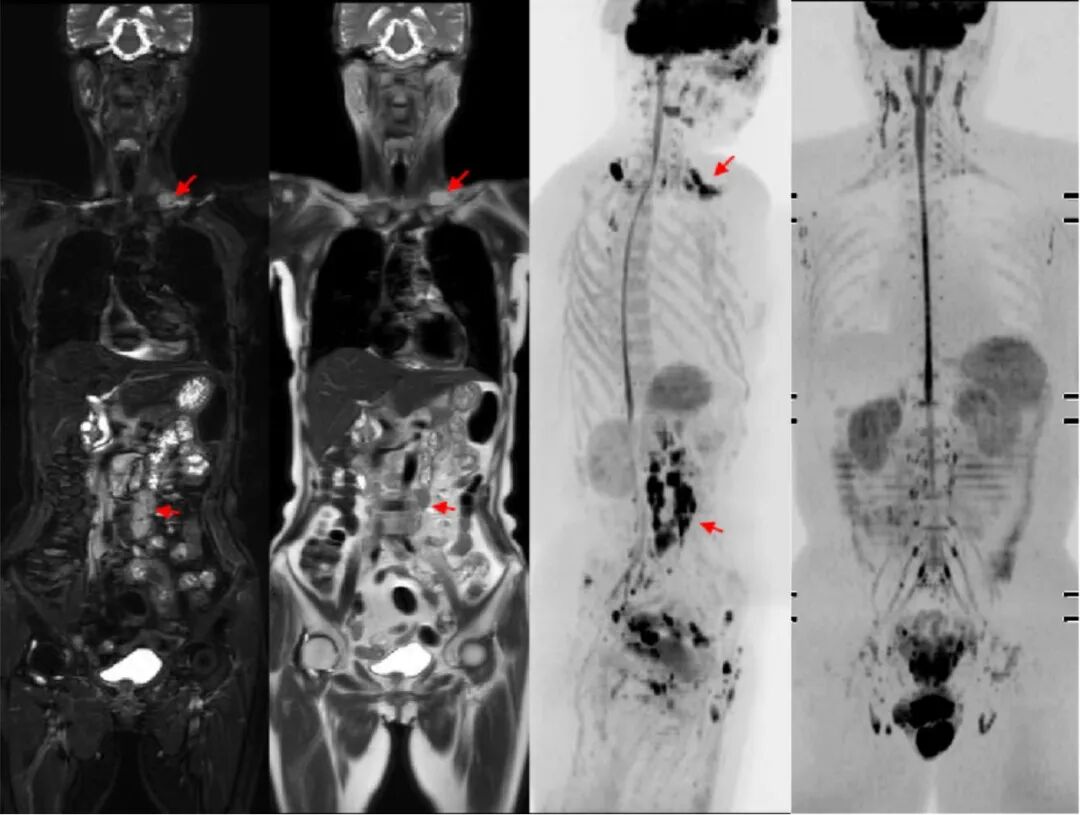

我院飞利浦128排256层光谱CT具有扫描速度快、图像清晰度高、辐射计量低、信息量大等特点。超宽的128排探测器,每圈扫描采集256层图像,对于全身及局部CT造影检查特别是心胸肺部等超高分辨扫描具有显著优势,其X线辐射比常规CT正常的辐射量大幅度减少;超高空间分辨率,可以显示1cm以下的微小病变,可进行大范围动态多器官的影像检查。

我院飞利浦1.5T磁共振(MRI)具有扫描速度快、成像效果清晰,后处理功能强大等优势,可以满足临床医师和患者的不同需求。磁共振应用广泛,主要用于人体各系统、各部位的肿瘤性病变、感染性病变、代谢性病变、先天畸形以及创伤性疾病的检查,对于神经系统、心血管、骨关节系统、肝脏、脾脏、胰腺、肾脏等腹部脏器以及前列腺、子宫等盆腔实质性脏器的检查独具优势。